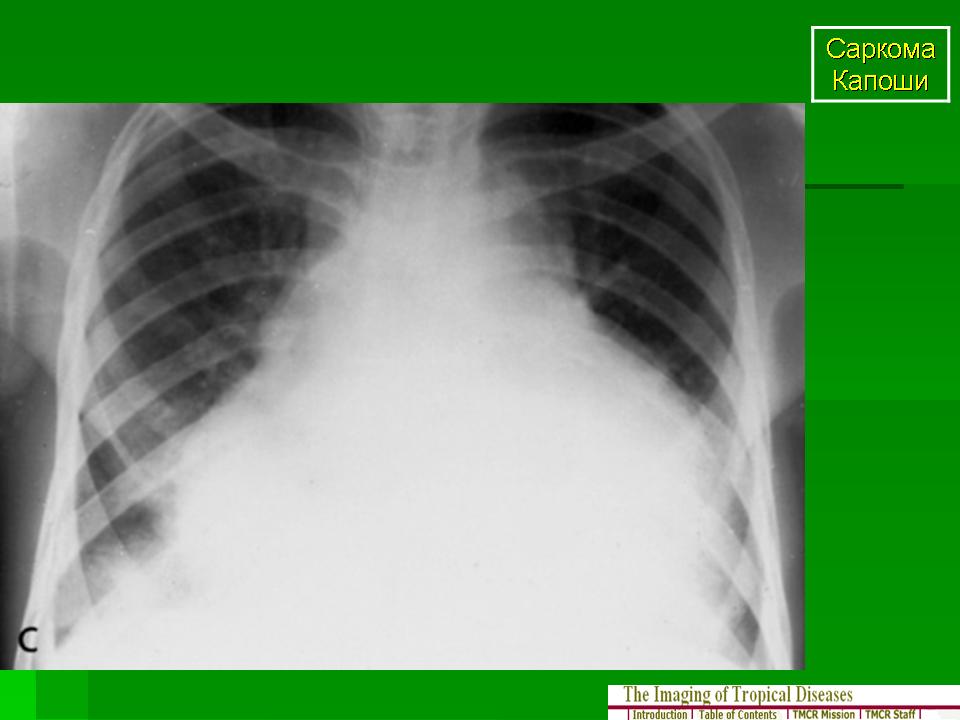

Саркома Капоши

Саркома Капоши — это многоочаговая злокачественная опухоль, которая поражает весь организм, происходит из эндотелия сосудов и обладает различным клиническим течением. Чаще всего болезнь проявляется поражением кожи, но способна затрагивать и слизистые оболочки, и лимфатическую систему, и внутренние органы (прежде всего легкие и ЖКТ). Описано четыре клинические формы саркомы Капоши: классическая (европейская), иммуносупрессивная, эндемическая (африканская) и эпидемическая (ассоциированная со СПИДом).

• Рентгенография грудной клетки.

Диапазон проявлений эпидемической саркомы Капоши весьма широк: от безболезненных кожных очагов до тяжелейшей диссеминированной болезни с поражением лимфоузлов и внутренних органов. Без лечения смерть в результате стремительного разрастания опухоли может наступить в течение нескольких недель. Злокачественный опухолевый рост был обнаружен при поражении саркомой Капоши легких. С появлением ВААРТ прогноз при саркоме Капоши значительно улучшился. Даже у пациентов с тяжелым поражением внутренних органов она позволяет добиться полной ремиссии.